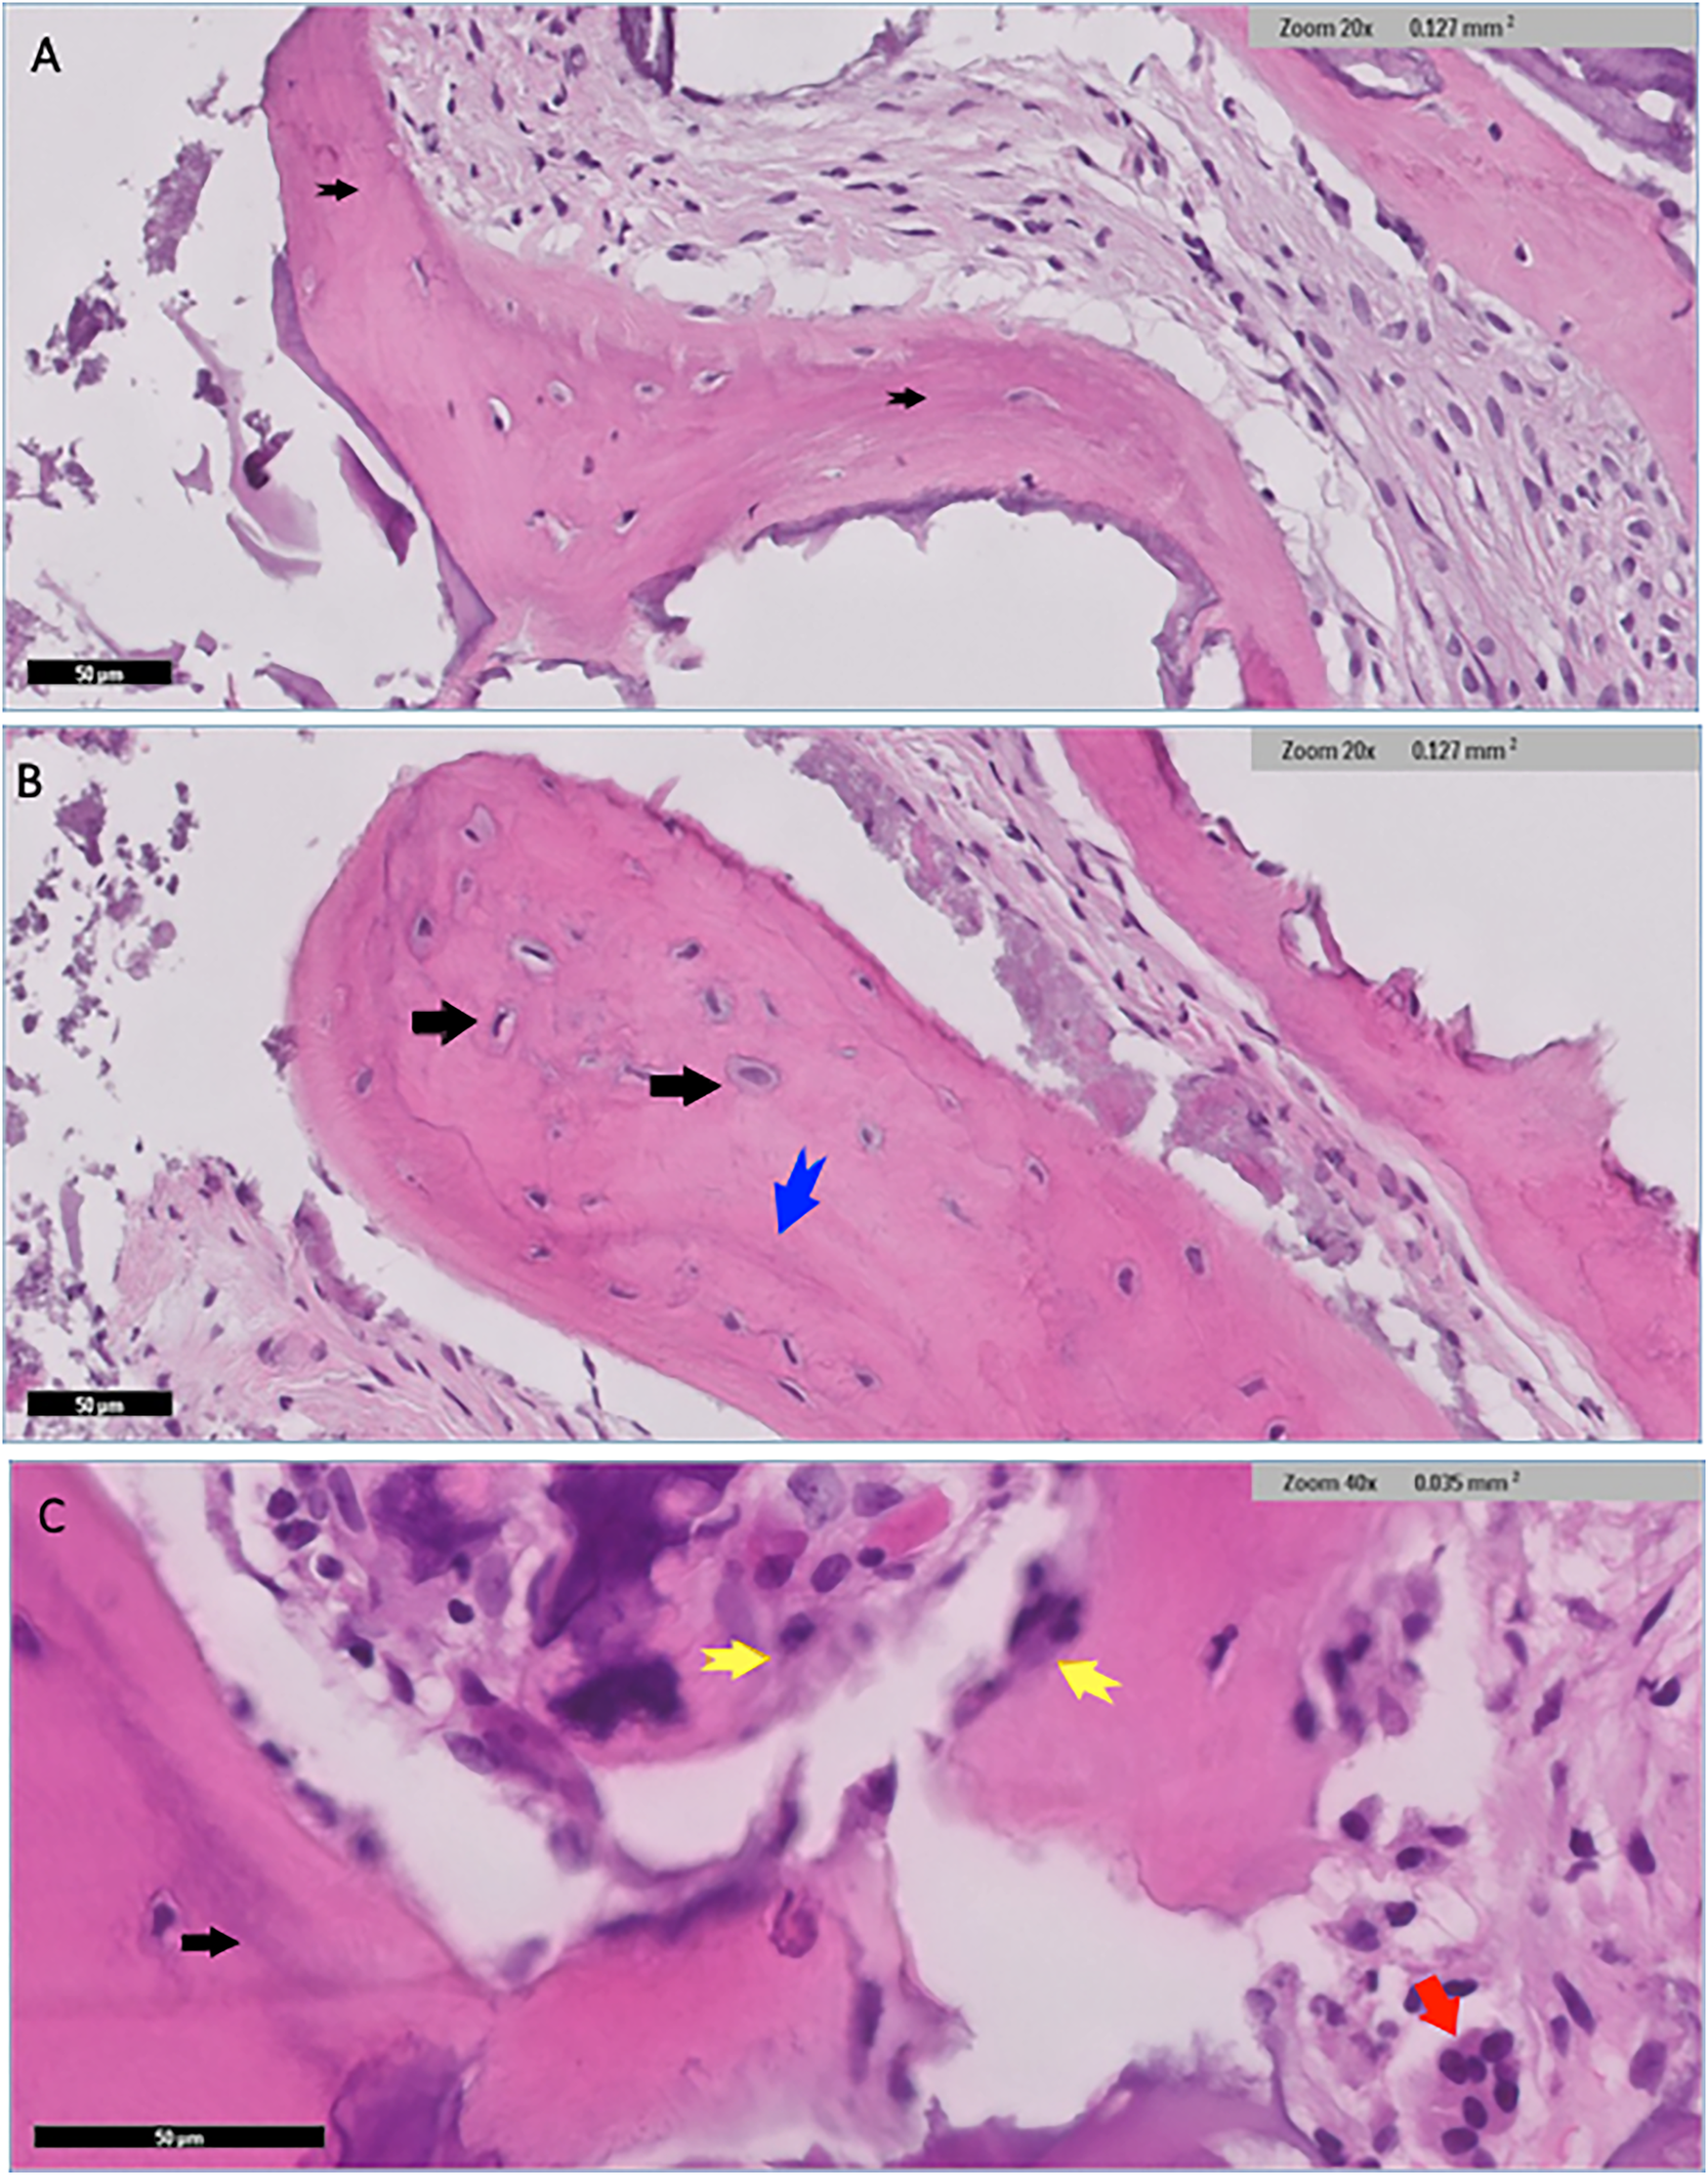

Figure 6

Histological findings for nuOss group showed scattered variably sized fragments of grafted bone embedded in dense fibrocollagenous stroma (black arrows) (A) well-preserved osteocytes were identified within the otherwise homogenous pink bone that lacked resting lines (black arrows) (B) the bone showed evidence of maturation in places blue arrow in (B) and black arrow in (C). Fragments of osteoid rimmed by well-developed osteoblastic rimming (original magnification ×40, yellow arrows) (C) Small fragments of residual grafted materials intimately surrounded by osteoclast giant cells (red arrow) were also present (C).

Histological examination for NuOss group revealed a loose collagenous background that supports an admixture of a viable lamellar cortical bone and inorganic matrix. The later shows focal partial integration with the native mature bone. High-power photomicrographs showed partial integration between the native lamellar cortical bone and the added bone graft material. Osteoclasts were identified at the edges of the integrated bony fragments in places (arrow) the rest of the section showed scattered fragments of the added grafted bone. variably sized fragments of grafted bone embedded in dense fibrocollagenous stroma were noted and well-preserved osteocytes were identified within the otherwise homogenous pink bone that lacks resting lines. The bone also displayed evidence of maturation in places (Figure 6).

Histologically, our study revealed different patterns of tissue response between the materials. In the NuOss group, we observed loose collagenous background with viable lamellar cortical bone and partial integration with the native mature bone. Osteoclasts were present at the edge of integrated bony fragments, consistent with normal bone remodeling processes.